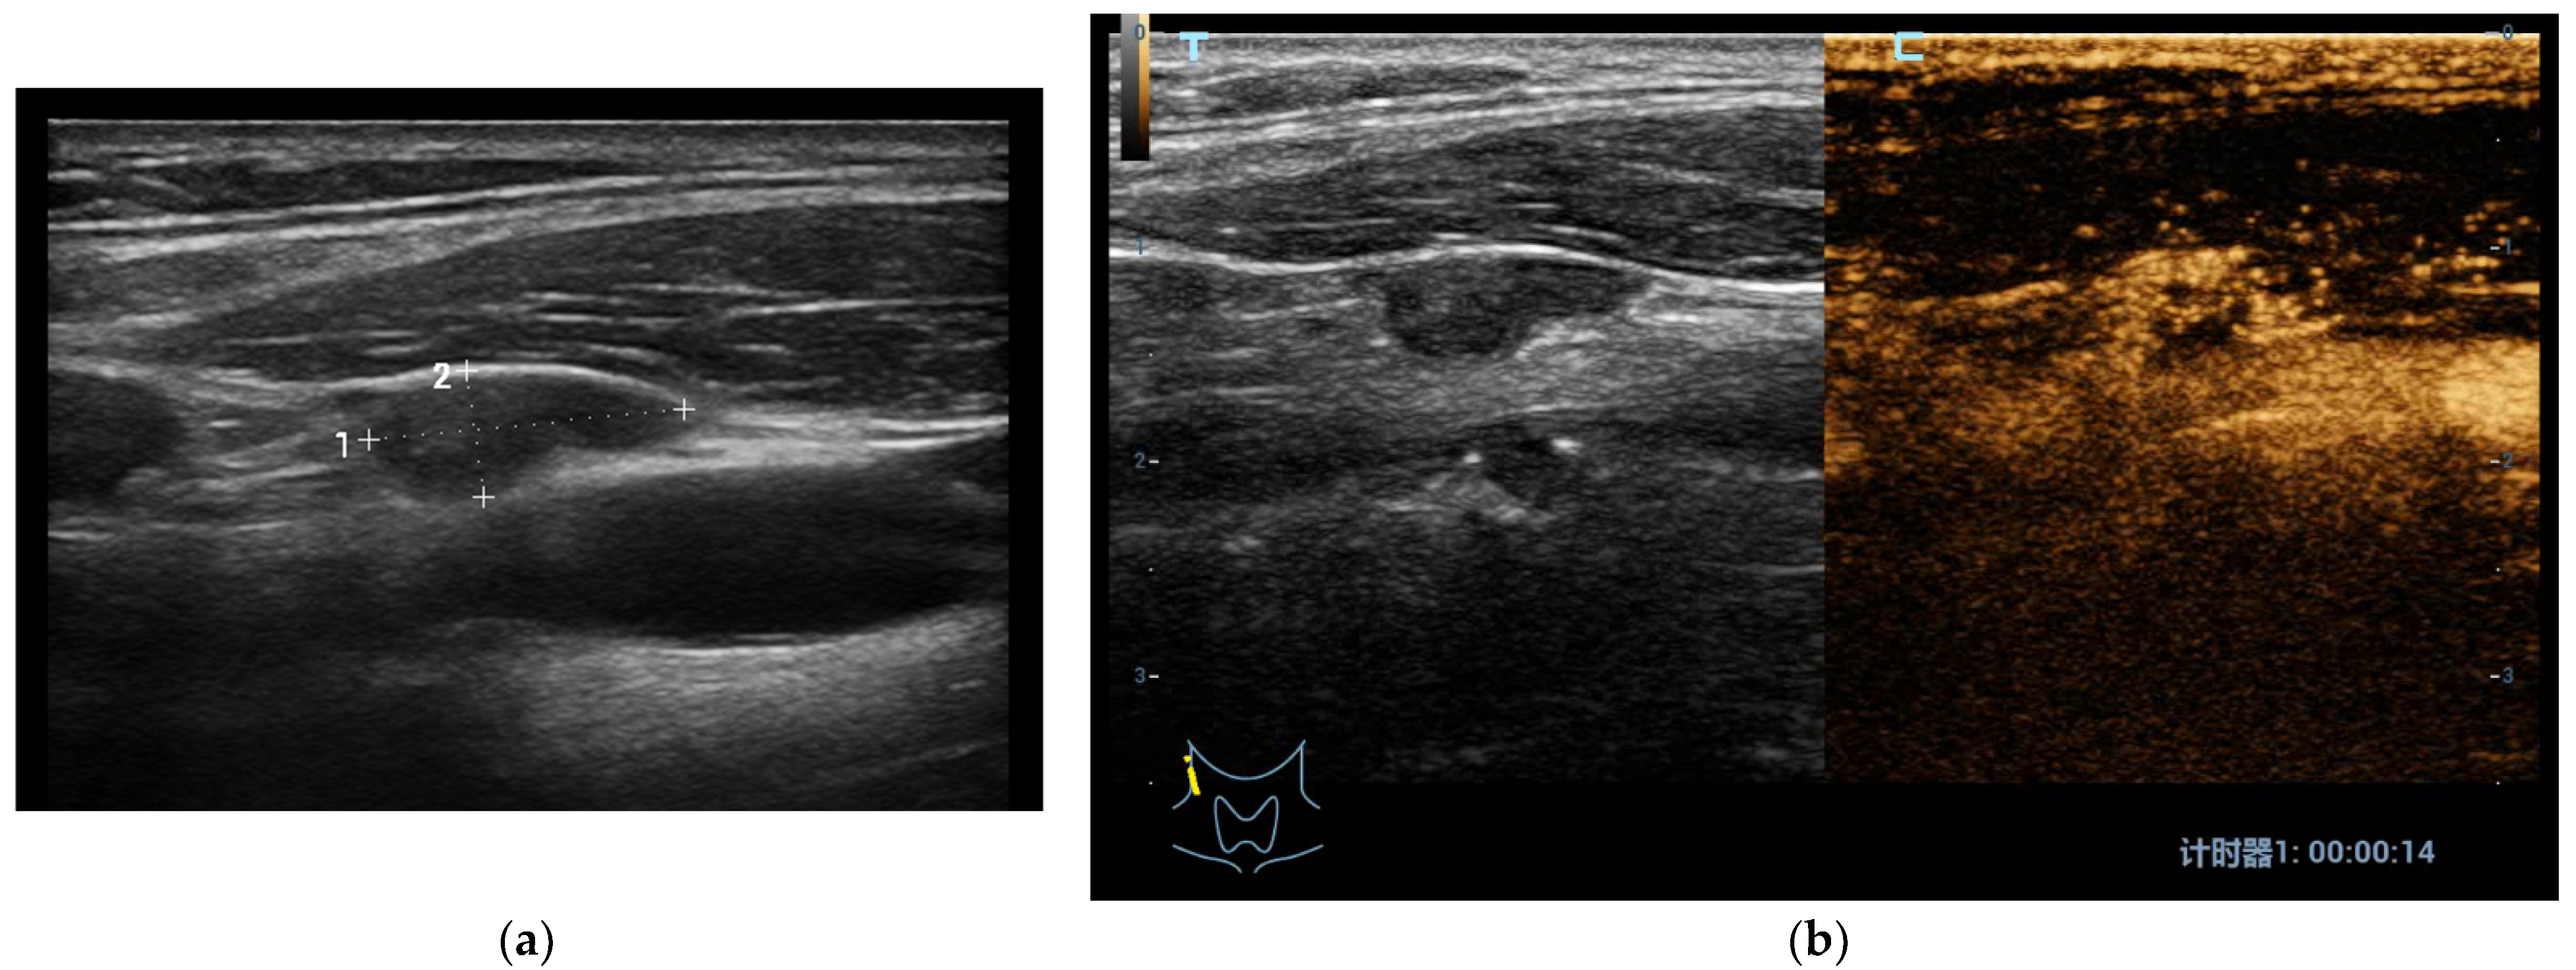

3.3. Evaluation of Lymph-Node Local Staging Using CEUS